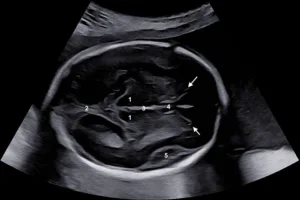

Em exames de ultrassom obstétrico, profissionais utilizam amplamente a biometria fetal para obter medidas do feto por meio de imagens de alta resolução. Eles comparam essas medidas com padrões de referência para avaliar o desenvolvimento fetal..

Durante a gravidez, é crucial monitorar o crescimento e desenvolvimento do feto para garantir que esteja ocorrendo conforme o esperado. A biometria fetal oferece uma maneira precisa e não invasiva de realizar essa monitorização, permitindo que os médicos avaliem parâmetros como o tamanho do feto, o tamanho da cabeça, o comprimento do fêmur e a circunferência abdominal.

Essas medidas são fundamentais para determinar se o feto está crescendo adequadamente e se há algum sinal de restrição de crescimento intrauterino, que pode indicar problemas de saúde subjacentes, como atraso no desenvolvimento ou problemas placentários. Além disso, a biometria fetal também é essencial para estimar a idade gestacional e prever a data provável do parto.